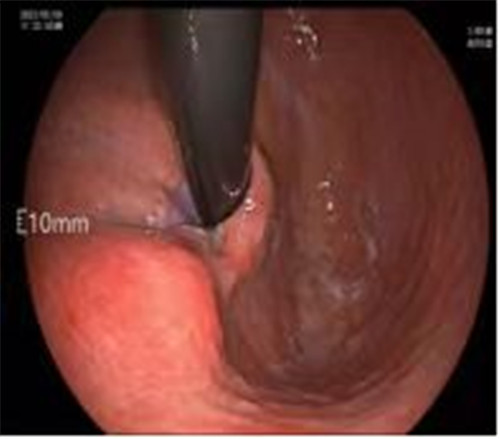

近期病例之一,圖片依次為:胃鏡、超聲胃鏡、ESE術(shù)中、術(shù)后、切下病變。

普通內(nèi)鏡是一種“直視”光學(xué)檢查,通過(guò)微型攝像頭將消化道管腔內(nèi)圖像實(shí)時(shí)清晰地呈現(xiàn)給檢查者;而超聲是一種“透視”的聲學(xué)檢查,通過(guò)人體組織不同的回聲特點(diǎn),對(duì)皮膚或粘膜以下的深部組織進(jìn)行觀察。超聲內(nèi)鏡則是兼兩者之所長(zhǎng),可以在直視的基礎(chǔ)上,了解表面以下的改變。

通過(guò)內(nèi)鏡切開(kāi)瘤體表面粘膜,分離后挖除瘤體,或以消化道全層切除的方法切除瘤體,并在內(nèi)鏡下縫合切口。與傳統(tǒng)手術(shù)相比,該項(xiàng)技術(shù)利用了人體自然通道,不會(huì)破壞人體結(jié)構(gòu),更加微創(chuàng)。不超過(guò)3cm向消化道腔內(nèi)生長(zhǎng)為主的良性或低度惡性粘膜下腫瘤(如間質(zhì)瘤、類癌、平滑肌瘤等),都可采用ESE治療。